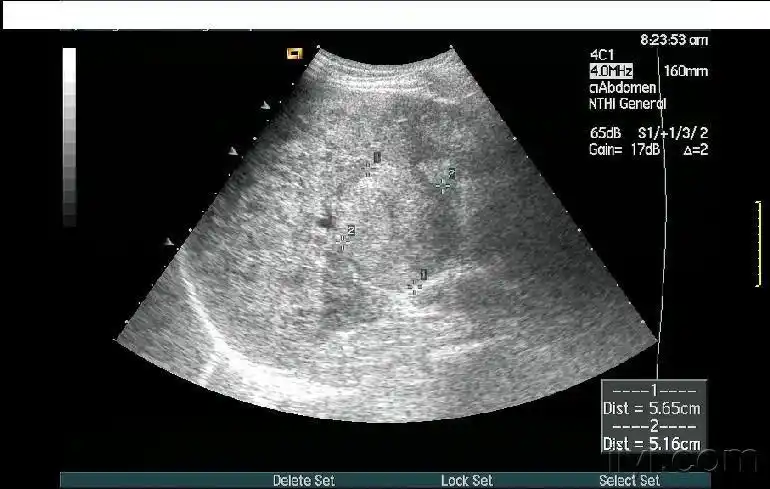

肝ca自发性破裂 - 超声医学讨论版 - 爱爱医医学论坛